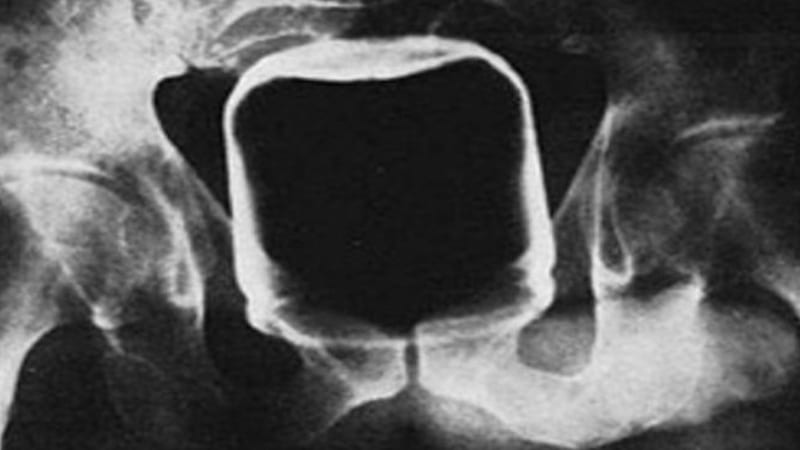

Have you ever seen one of those dildos that is in the shape of a fist? Yep! That’s what’s in there. The item might be marketed towards anal play, but without a flared-base, it’s just not safe and stuff like … this … can happen.